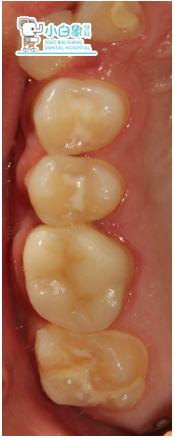

检查:颌面部查未见异常,口内查:牙列不齐,16近中临面龋坏达髓腔,近中缺损至龈下,探诊(-),温度测试无反应,叩(土),牙龈无红肿。36合面大面积缺损,髓腔暴漏,探诊(-),温度测试无反应,叩(+),牙龈无红肿。17,26,27,37,46,47合面龋坏达牙本质深层,探诊敏感,温度测试正常。14,24合面龋坏达牙本质浅层,探诊(-),温度测试正常。15,25,34,35,44,45萌出,窝沟较深,着色,无龋坏。12,22舌侧窝沟龋坏达牙本质深层,探诊敏感,温度测试正常。全口卫生差,软垢覆盖牙面二分之一,牙龈无红肿。

治疗过程:a.16去腐质,揭髓顶,拔髓未见,冲洗,隔湿干燥,封木榴油。一周复诊根充,局麻下切龈,制备牙体,扫像,设计,研磨,上釉,粘结,调合。

嵌体粘结